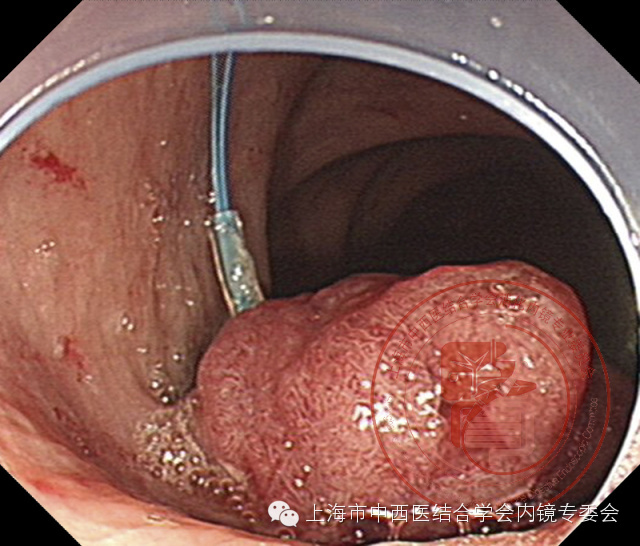

亚蒂息肉

套扎息肉基部